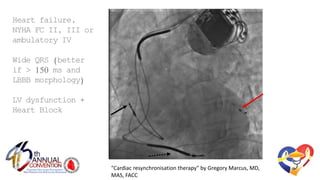

"Cardiac resynchronisation therapy" by Gregory Marcus, MD,

MAS, FACC

Heartfailure,NYHA

FC II,IIIorambulatory

IV

w/Wide QRS (better

if > 150 ms andLBBB

morphology)

----

LV dysfunction+

HeartBlock